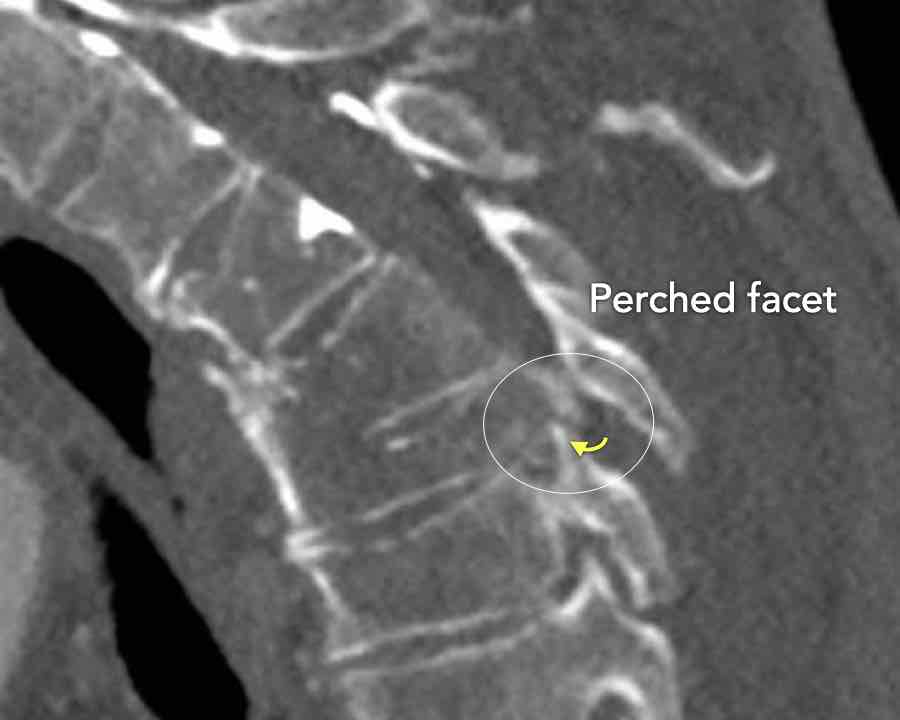

Scroll through the images

Findings:

- Perched facet joints (yellow curved arrows), so think of C injury.

- Posterior displacement of the vertebral bodies in the midline.

- Secondary A4 injury of the vertebral body.

Conclusion

Type C + A4 injury